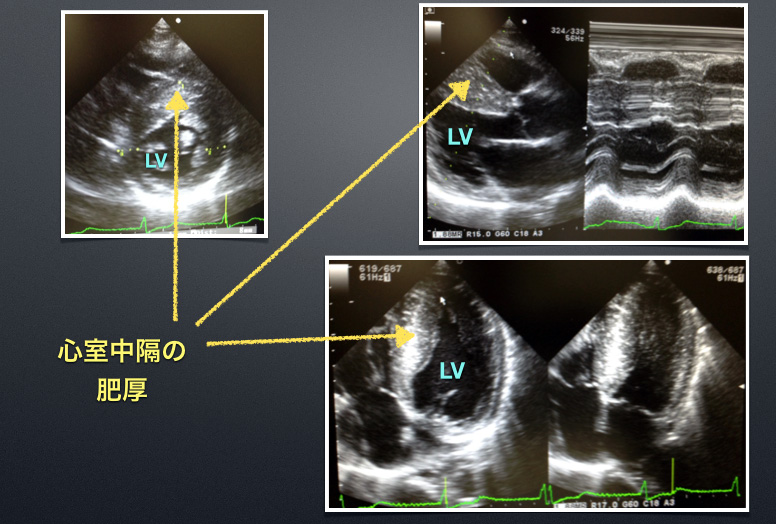

心エコーを提示します。

E146hcmcpa_vf

クリックすると、拡大します。